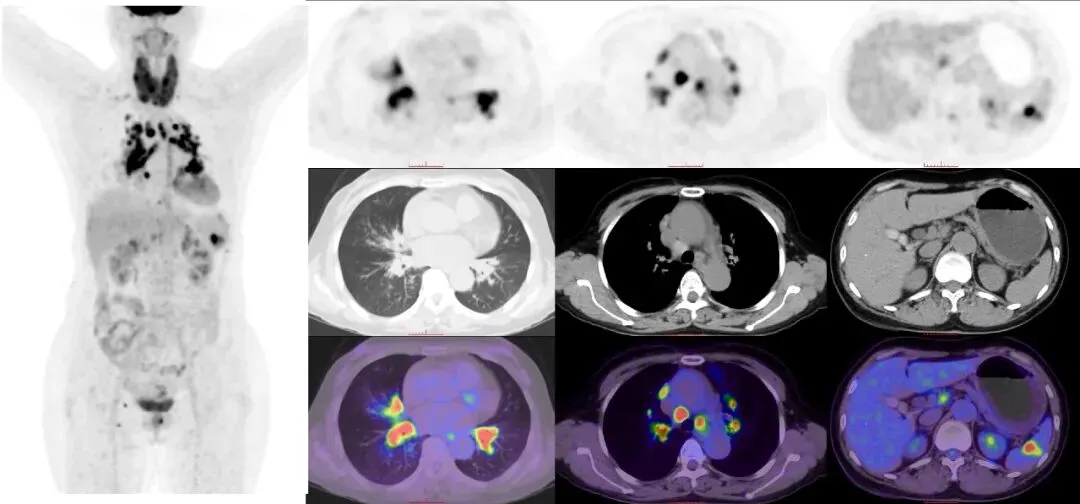

CASE 3

女,58岁,胸闷气喘1年,再发加重2月。患者自诉于1年前无明显诱因出现胸闷气喘,当时无咳嗽,无胸痛不适,未予以重视及就诊;2月前患者再次出现胸闷气喘,伴咳嗽咳痰、白色粘痰,呼吸困难,偶有咯血,无明显胸痛,无发热,当地医院查胸部CT示右侧肺门增大,纵隔多发肿大淋巴结,两上肺感染性病变。我院18F-FDG PET/CT示双肺门及纵隔多发肿大淋巴结,糖代谢异常增高;脾脏内结节状糖代谢增高;双肺斑片状影,糖代谢增高。双侧甲状腺肿大,糖代谢增高。